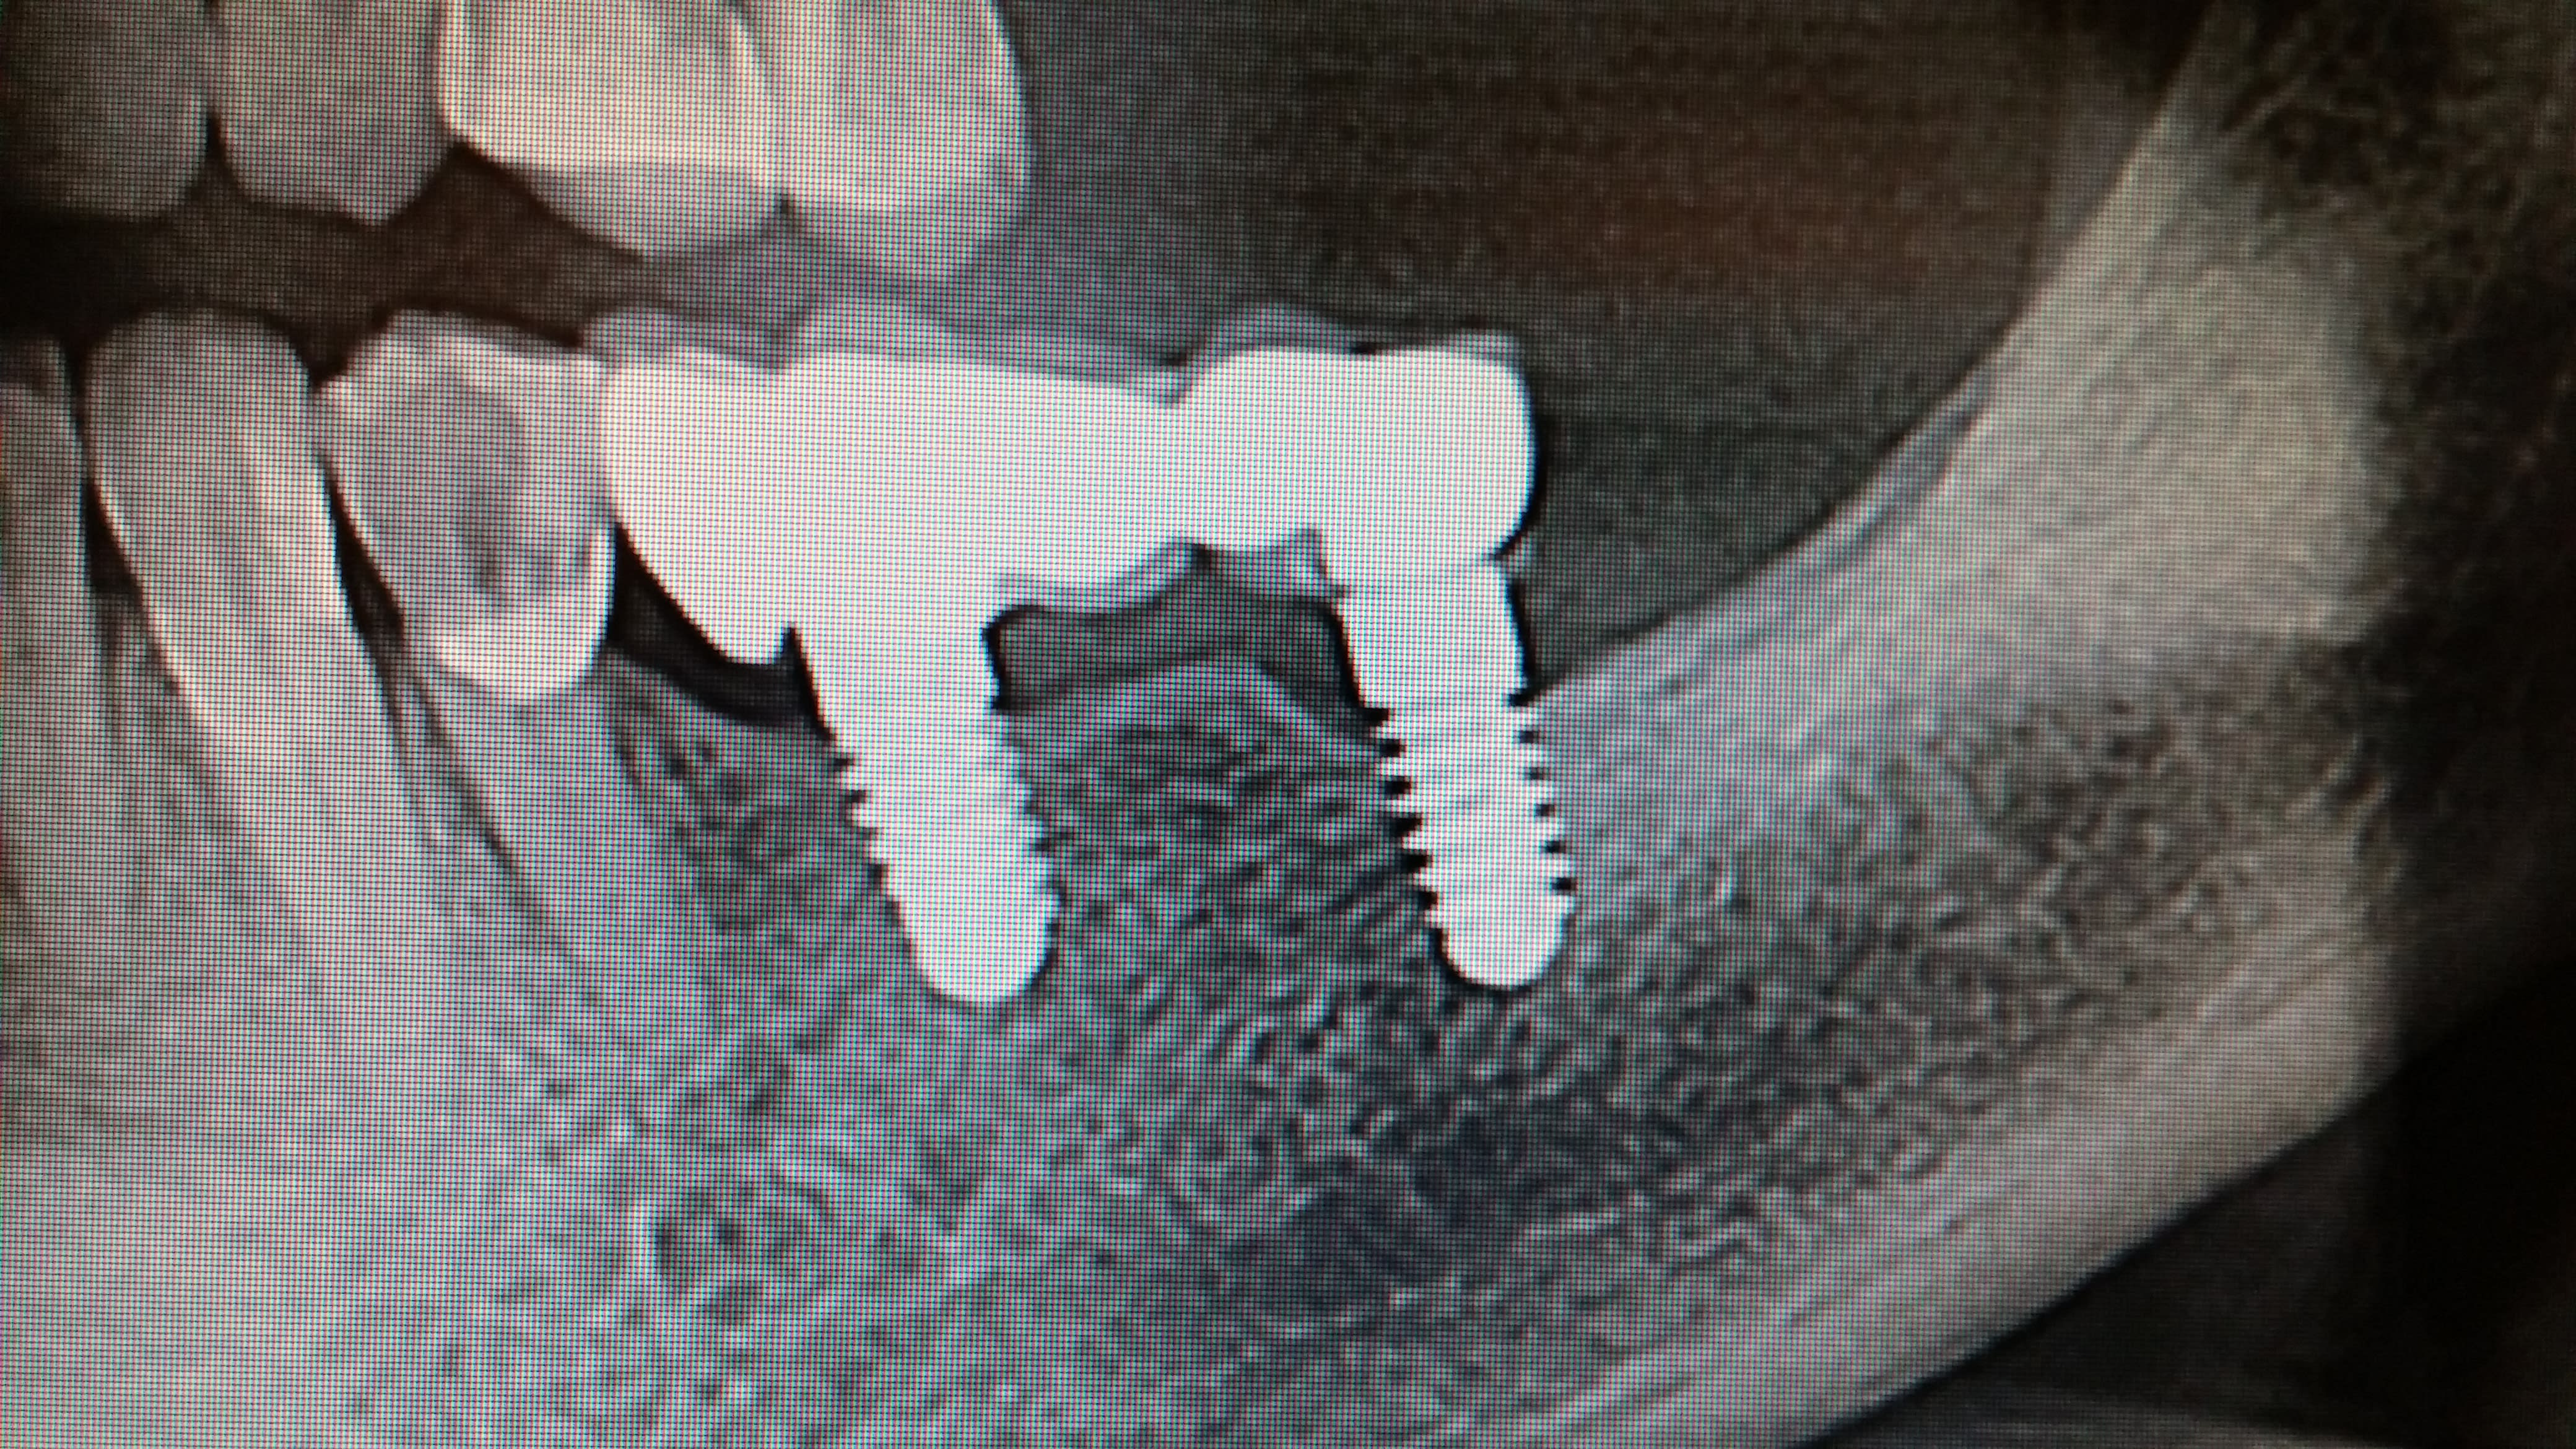

Vu hier en consult

Posés en Italie il y a 12+ ans

Vis cassée en mésial, "scellé" un urg il y a 2 mois dans une autre clinique, ça bouge encore...

Je connais pas ces implants...